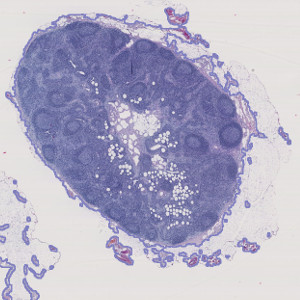

All relevant lymph node tissue is automatically outlined (in purple) for further analysis.

Step 1: Tissue Detect: Outlines tissue on the slide for further analysis.